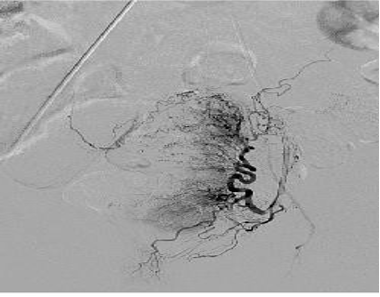

导管技术与子宫肌瘤相似,但是血管栓塞的终点应该是完全造影剂停滞【Lohle et al. 2007】

50岁,严重经期出血 栓塞 微球400μm ,每侧2ml,然后改 500μm 每侧1ml

3个月后随访,经期出血减少